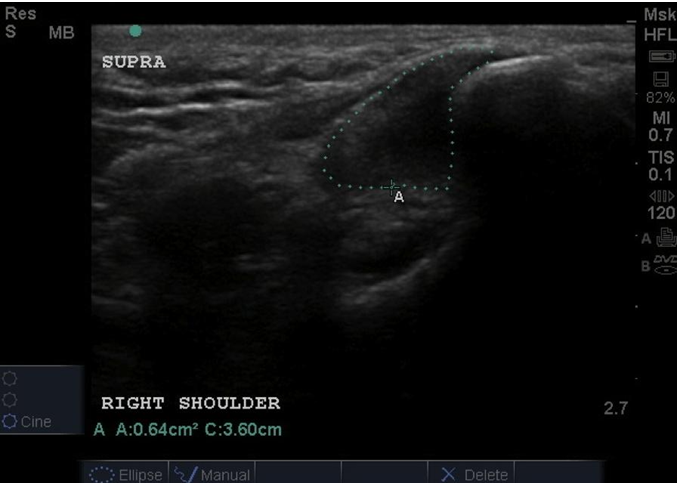

Results: Dogs aged 4 months to 14 years (average 6.5 years; median 6 years) were diagnosed with ST. Performance and sporting dogs were 39.4% of the population, with 58.1% of them being agility dogs. Pain was elicited on palpation of the supraspinatus tendon in 49.3% of dogs. Shoulder radiographs in 283 dogs showed mineralisation in 13% of cases. MRI of the shoulder was performed in 31 cases and revealed findings indicative of ST, including hyperintensity of signal on T1 weighted image (or “spin-lattice”) and Short T1 Inversion Recovery (STIR) sequences of the supraspinatus tendon at its insertion on the greater tubercle and mineralisation of the supraspinatus tendon. Common ultrasonographic findings included increased tendon size (76%), irregular fibre pattern (74%), and non-homogeneous echogenicity (92.5%). The most common findings on shoulder arthroscopy were supraspinatus bulge (82.2%) and subscapularis pathology (62.4%). Elbow pathology was recorded in 54.5% of dogs. Treatment outcomes showed 74.6% of dogs failed to respond to non-steroidal anti-inflammatory drugs (NSAID) and 40.8% failed to respond to rehabilitation.